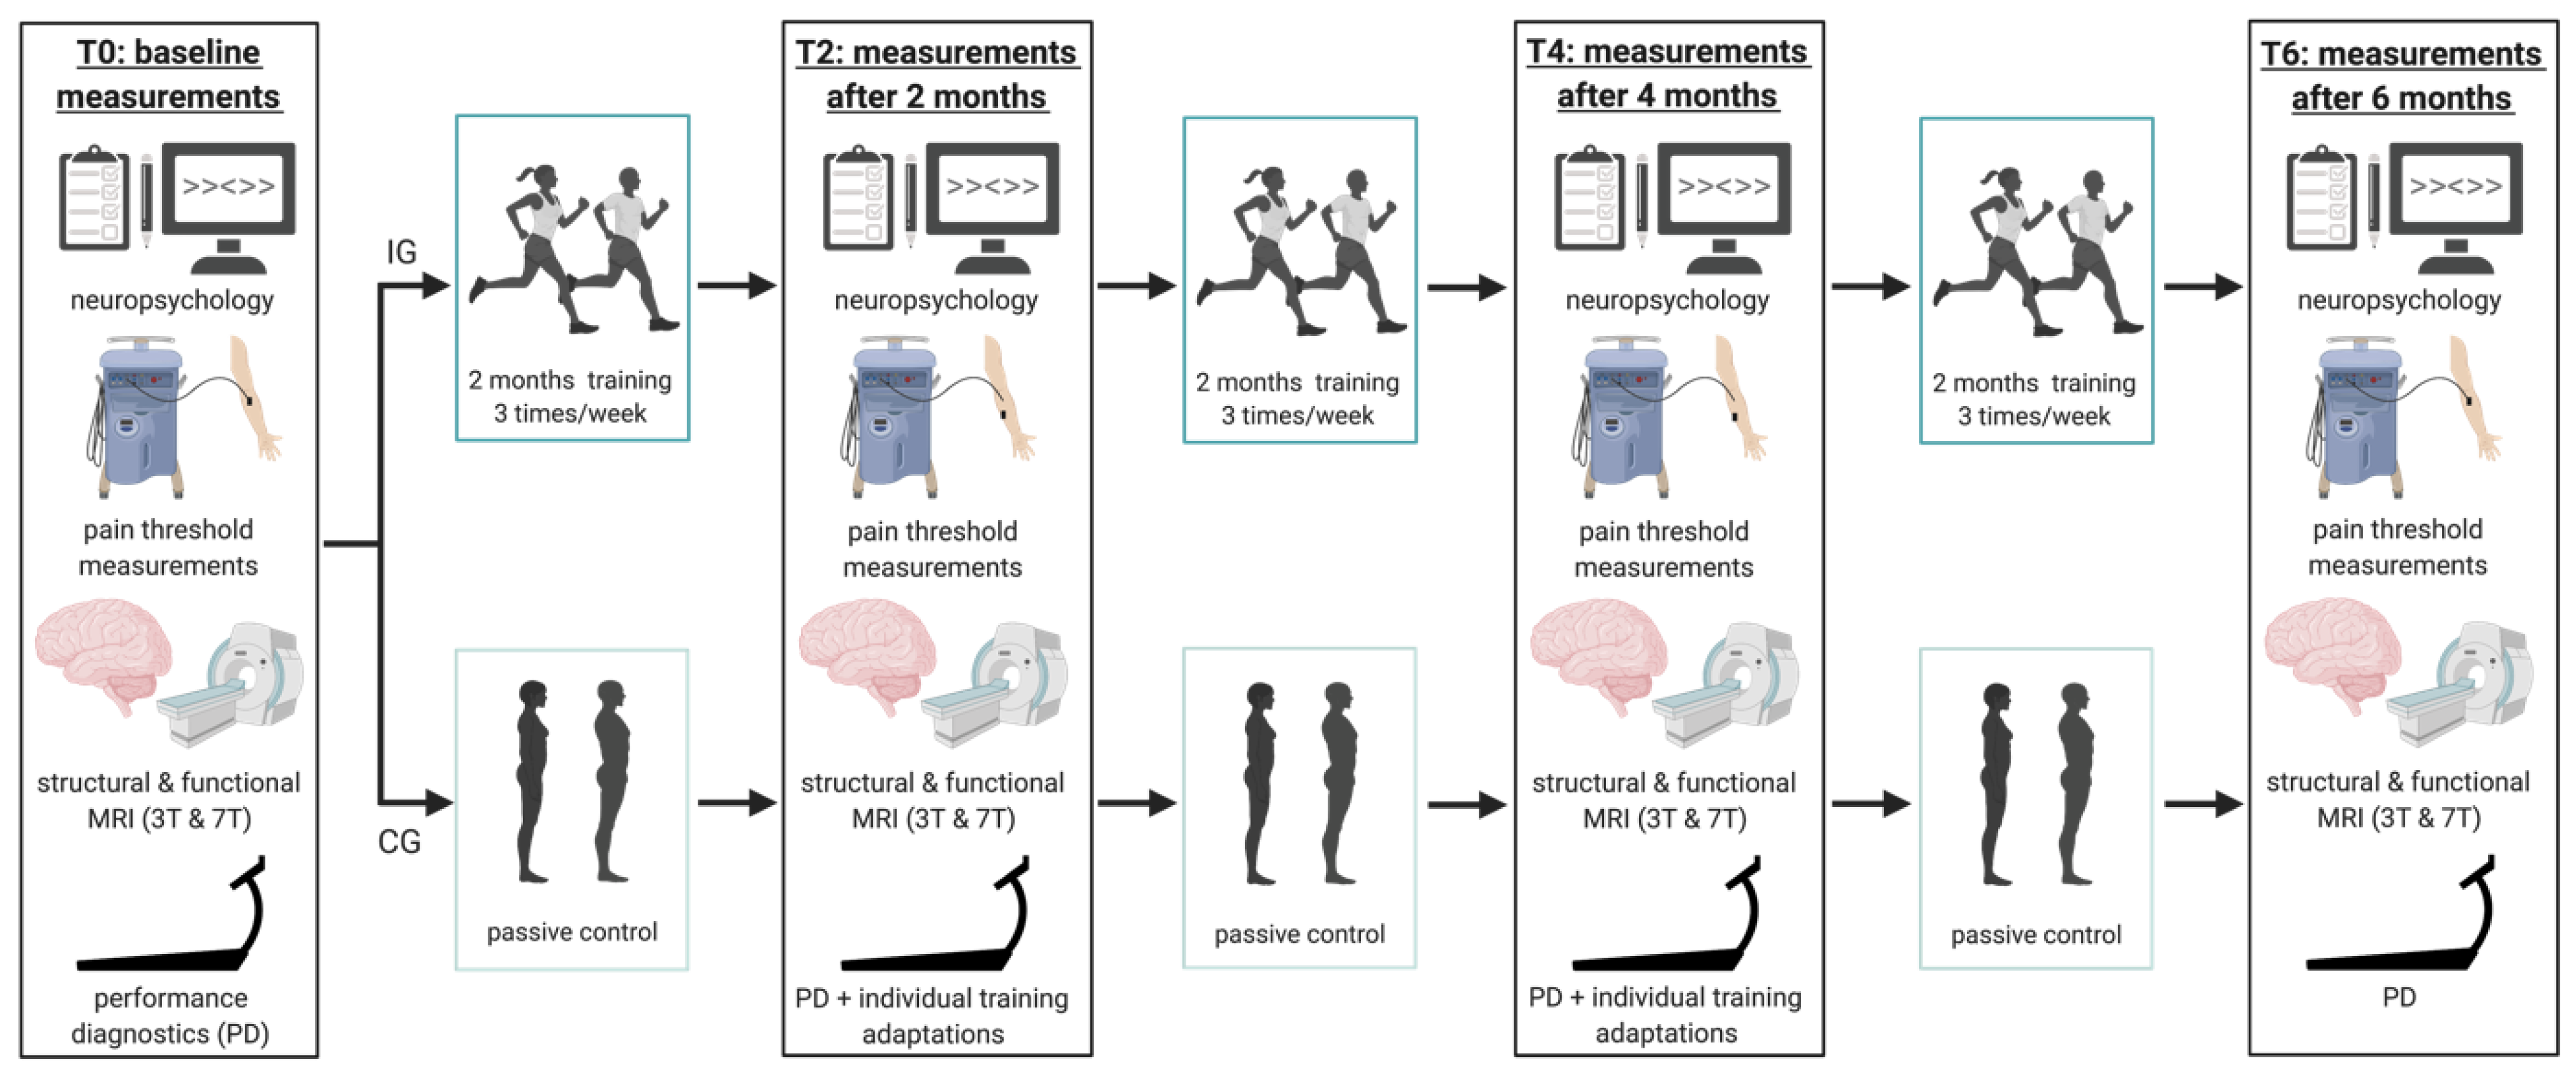

3.4. Structural MRI